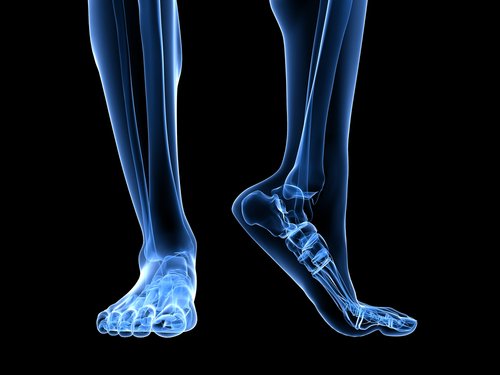

Anatomia do pé

Há várias estruturas anatômicas implicadas que podem causar a sobrecarga da fáscia plantar.

O tendão de Aquiles é um ligamento que se insere desde os músculos gastrocnêmios, comumente chamados gamelos, e o sóleo até o osso do calcanhar. Uma retração do tendão de Aquiles causará um aumento de pressão no calcâneo, com o consequente aumento de pressão no ligamento arqueado.

Outro fator a levar em conta na estrutura anatômica é o apoio do pé, ou seja, a forma como o pé toca o chão. Os pés planos ou com tendência pronadora causam um alongamento maior da fáscia plantar, aumentando o risco de rupturas pelo aumento da pressão no tecido.